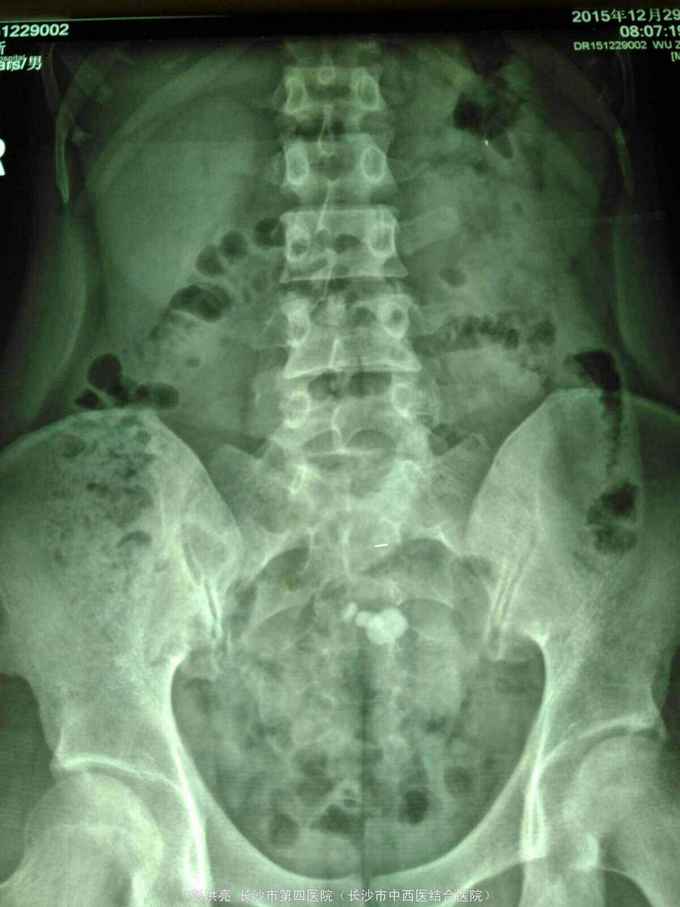

男性,25岁,左腰痛入院。2年前在外院发现左侧盆腔异位肾并肾盂输尿管移行处结石行腹腔镜下切开取石术。现CT示左侧盆腔异位肾并多发结石。术前其他检查正常。

请问该患者如何处理。